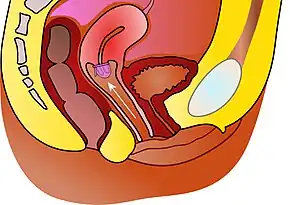

The cervical cap is a form of barrier contraception. A cervical cap fits over the cervix and blocks sperm from entering the uterus through the external orifice of the uterus, called the os.